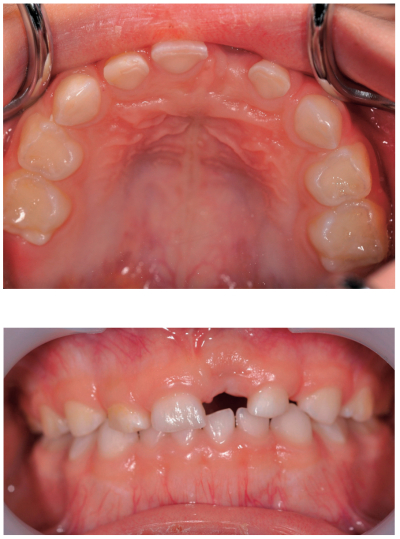

4歳の女児。3か月前に外傷により上顎左側乳中切歯が脱落し審美不良を訴え来院した。創傷治癒後の口腔内写真を別に示す。

適切な対応はどれか。1つ選べ。